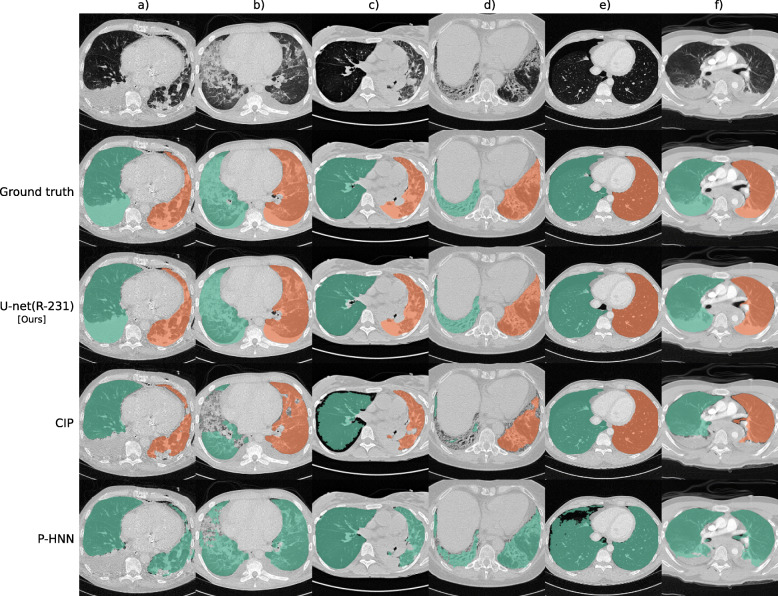

Fig. 2.

Segmentation results for selected cases from routine data. Each column shows a different case. Row 1 shows a slice without lung masks, row 2 shows the ground truth, and rows 3 to 5 show automatically generated lung masks. Effusion, chest tube, and consolidations (a); small effusions, ground-glass and consolidation (b); over-inflated (right) and poorly ventilated (left), atelectasis (c); irregular reticulation and traction bronchiectasis, fibrosis (d); pneumothorax (e); and effusions and compression atelectasis (trauma) (f)